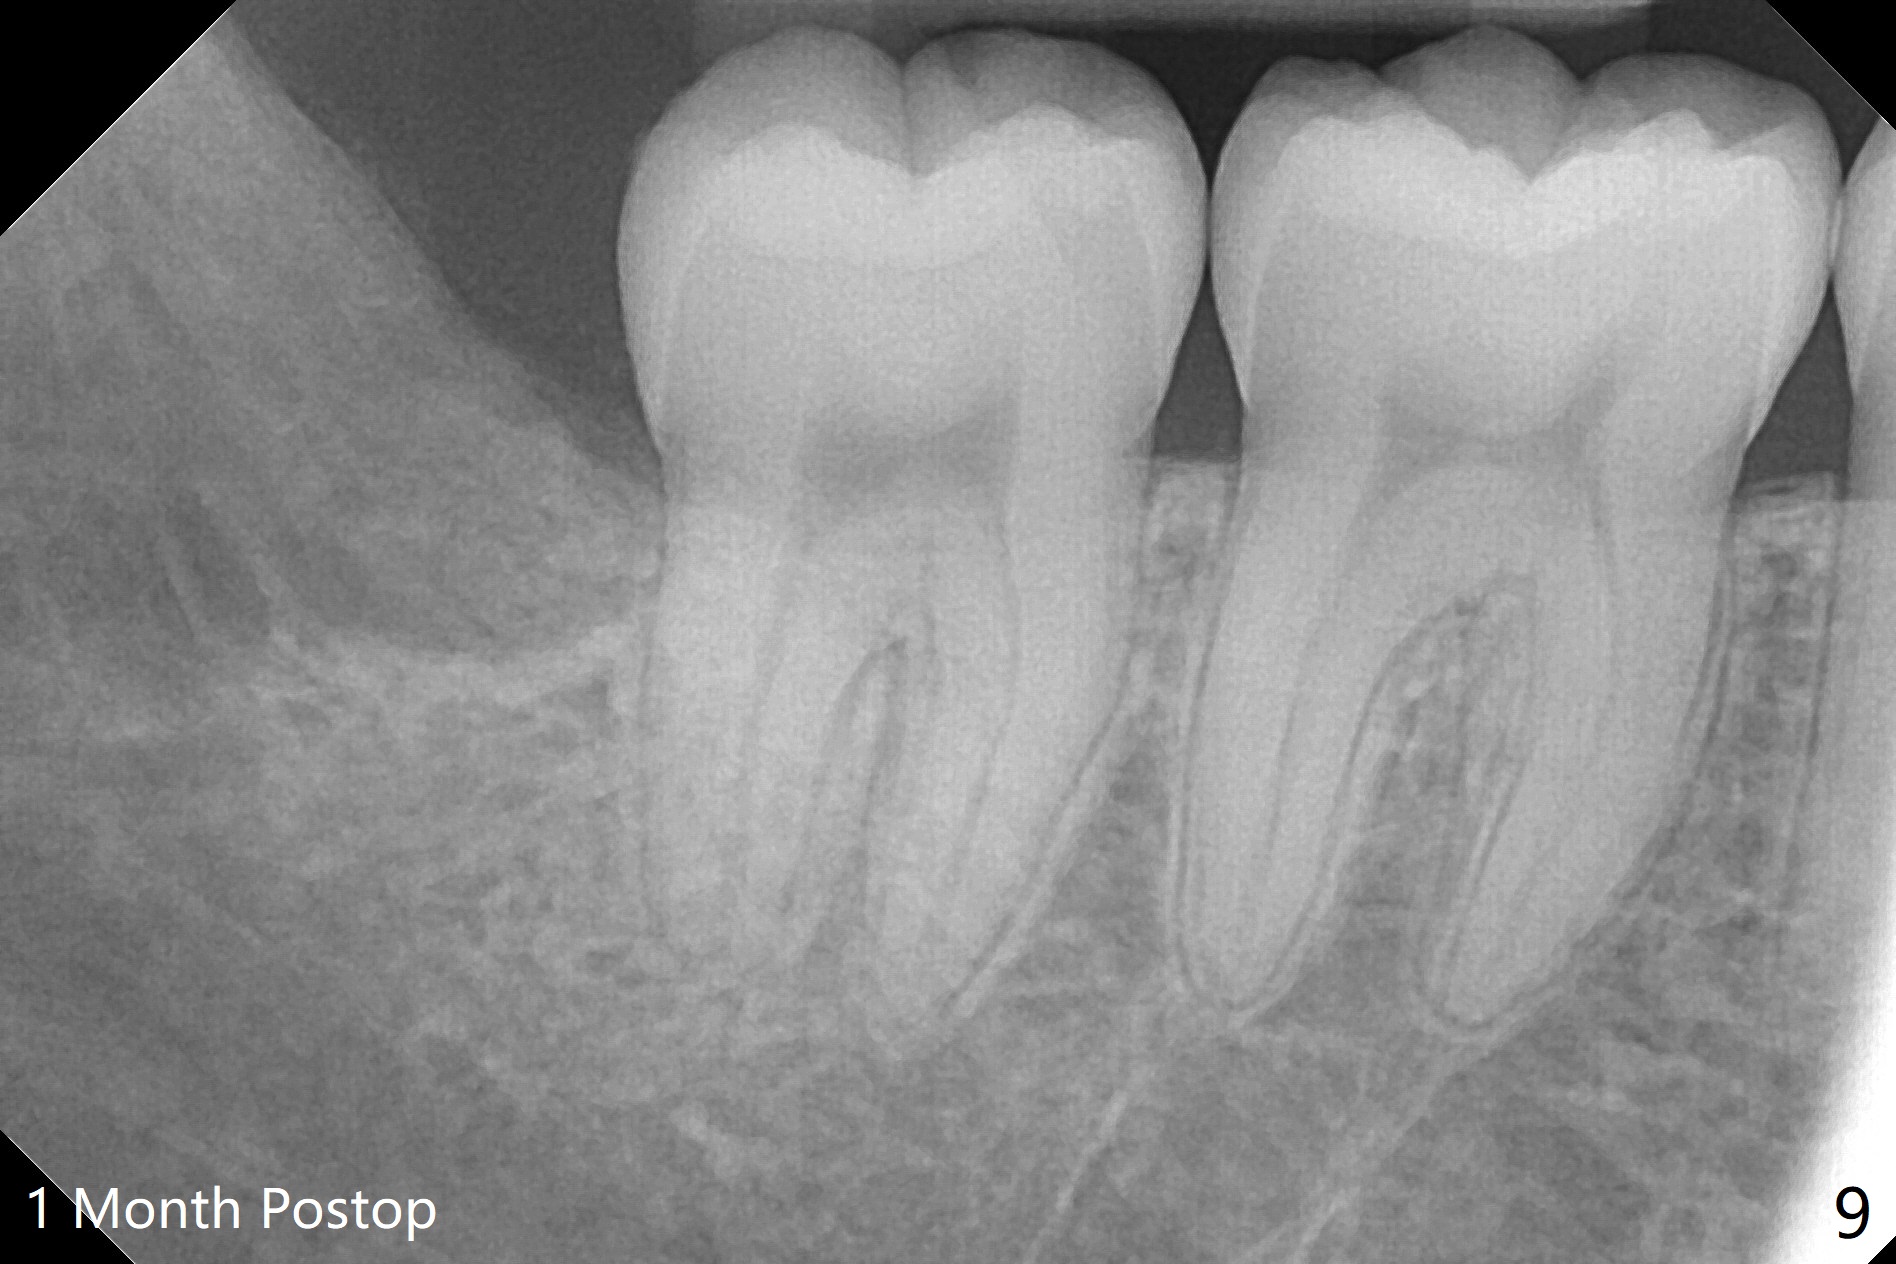

In fact the tooth #32 is extracted first; the defect involves the distobuccal aspect of the tooth #31 (Fig.4 *). An intraop PA is taken after extraction to confirm whether a broken surgical fissure bur tip retains or not; the distal lamina dura of #31 is low (Fig.5 *). It is expected to increase after cocktail bone graft (Fig.5' arrow). As planned, the bone cement (Fig.6 C) and allograft (G) are placed in the distal and mesial portions of the socket; between them is Osteogen Plug (O). Another piece of Osteogen Plug (as collagen membrane for bone graft) is placed on the top of the socket before suturing with 4-0 Plain Gut (Fig.7,7' O). Also note the bone graft being placed distobuccal (CT study) to #31 (Fig.7' red dashed line) to reduce possibility of future periodontitis. The patient returns 15 days postop with chief complaint of mild pain since extraction, although the wound looks normal. The transverse cortex connecting to the lamina dura (Fig.5 *) is obliterated when allograft is placed (Fig.7 G). The part of the graft remains in place 1 month postop (Fig.9) in spite of wound dehiscence (Fig.8). The bone graft loss is indicated by the fact of the reappearance of the transverse cortex (Fig.9). In the same appointment, the tooth #17 (Fig.10) is being extracted (Fig.11), leaving a defect mesiobuccal (Fig.12 *) to distal (curette). Part of Osteogen plug (Fig.13 O) is stretched to cover the mesially placed allograft (Fig.14 G). One quarter of Collagen plug is placed over the Osteogen plug (Fig.13 O) before 4-0 PGA suturing. There is bone regeneration 1 year postop (Fig.15,16).